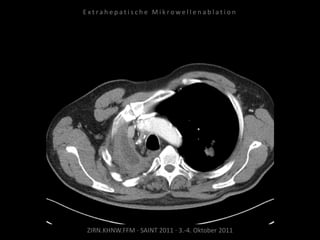

Patient: Weiblich, 71 Jahre

Diagnose: Ovarial-Ca,

größenprogredienter Lymphknoten

zwischen Herz und Leber als einzige

Metastase.

Bildgebung vor MWA:

CT 14.03.2011

Situation:

Nur 1 Metastase, diese ist jedoch

progredient. Kritische Lage in

Herznähe.

Ablation am 24.03.2010:

2 Nadelpositionen.